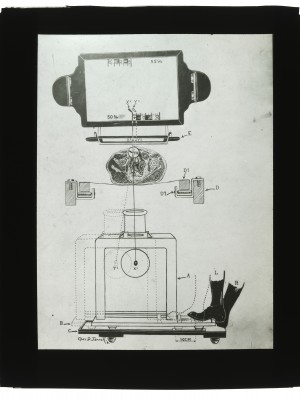

Dr. Edwin Ernst, an only child born to St. Louis residents Charles and Catherine Ernst, was a notable Roentgenologist, a physician who specializes in radiological work. Dr. Ernst studied at Washington University in St. Louis and later at Moravian College in Bethlehem, Pennsylvania earning his advanced degrees. For two years he served as a resident physician at the St. Louis Mullanphy Hospital before leaving to pursue a private practice. When the United States formally entered the war in 1917, Ernst left St. Louis to become chief radiologist at Base Hospital 21. He was discharged honorably in 1919 with the citation of Major. His collection consist of x-ray images taken at Base Hospital 21 as well as drawings of radiological equipment and photographs.